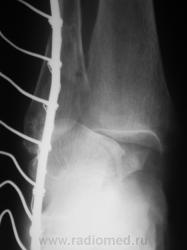

Перелом наружной и задней лодыжек. Подвывих в голеностопном суставе кнутри. Подвывих в тараннопяточном суставе. Разрыв дистального межберцового сочленения.

Переломы латеральной и медиальной лодыжек, пронационный подвывих в голеностопном суставе, латеральный подвывих в таранно-пяточном, разрыв межберцового синдесмоза.

Almo правильно задал вопрос, это касается терминологии. Про вывих стопы говорят, когда имеется вывих в г/ст суставе, а подтаранный N. Если имеется вывих в голенностопе и в подтаранном в противоположные стороны, т.е. смещается только таранная кость, говорят о вывихе таранной кости. Данный случай относится именно к последнему.